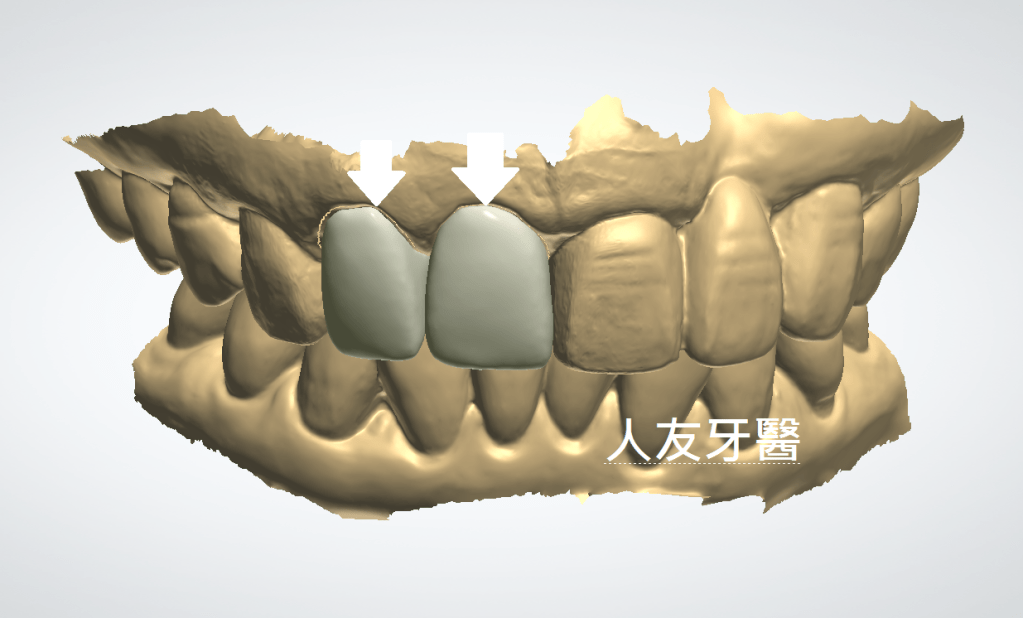

3.3D電腦掃描設計擁有更精準的密合度,保護牙根並延長牙齒壽命。(下圖)

4.堅固耐磨,適用前牙及後牙(下右圖)。

在詳細討論後患者決定透過數位掃描及電腦設計製作氧化鋯牙套修復上顎前牙,確保牙齒顏色均勻自然而且強度更高,耐磨度更高,完成後患者表示非常滿意。